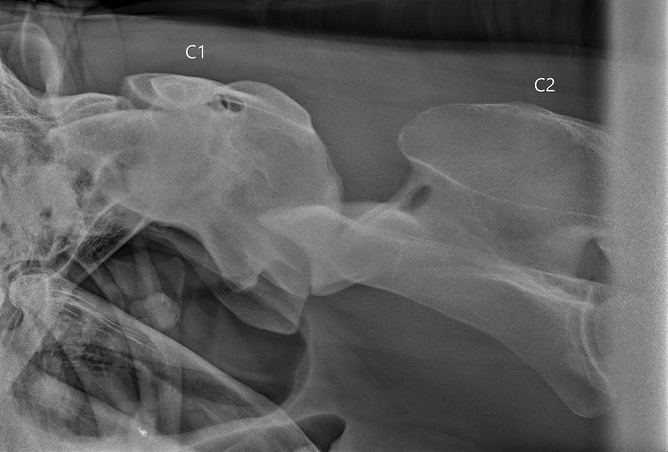

Investigation of cervical dysfunction and neck pain requires a full clinical and lameness examination and neurological assessment. The use of radiography and ultrasonography along with nuclear scintigraphy (bone scan) and if available, Computed Tomography (CT) can help identify lesions present. Radiographs provide a good baseline screening tool for horses with neck pain or dysfunction, however, some changes present on older horses are common and may not always be clinically significant. Boney changes, vertebral fractures, vertebral abnormalities and anatomical changes may be identified.